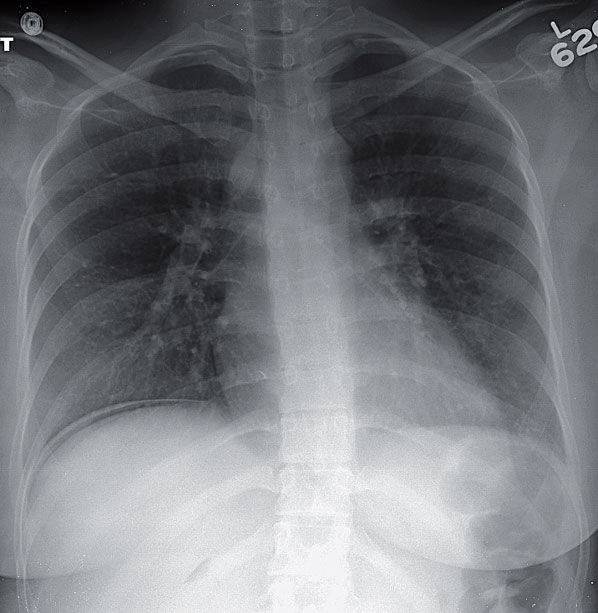

- Chest radiograph shows a crescentic lucency below the right hemidiaphragm

- Another lucency is seen above the right kidney. This gas within the hepatorenal fossa has been called the “Doge’s cap” sign, as it is said to resemble the headgear of the former leaders of Venice.

Curvilinear lucency at the level of the right hemidiaphragm may represent either a subpulmonic pneumothorax or free intraperitoneal gas.

- Signs of pneumoperitoneum on chest radiography include curvilinear lucency beneath the hemidiaphragm, gas outlining the right border of the liver on a left lateral decubitus, Doge’s cap, continuous diaphragm sign, and generalized increased lucency overlying the liver.